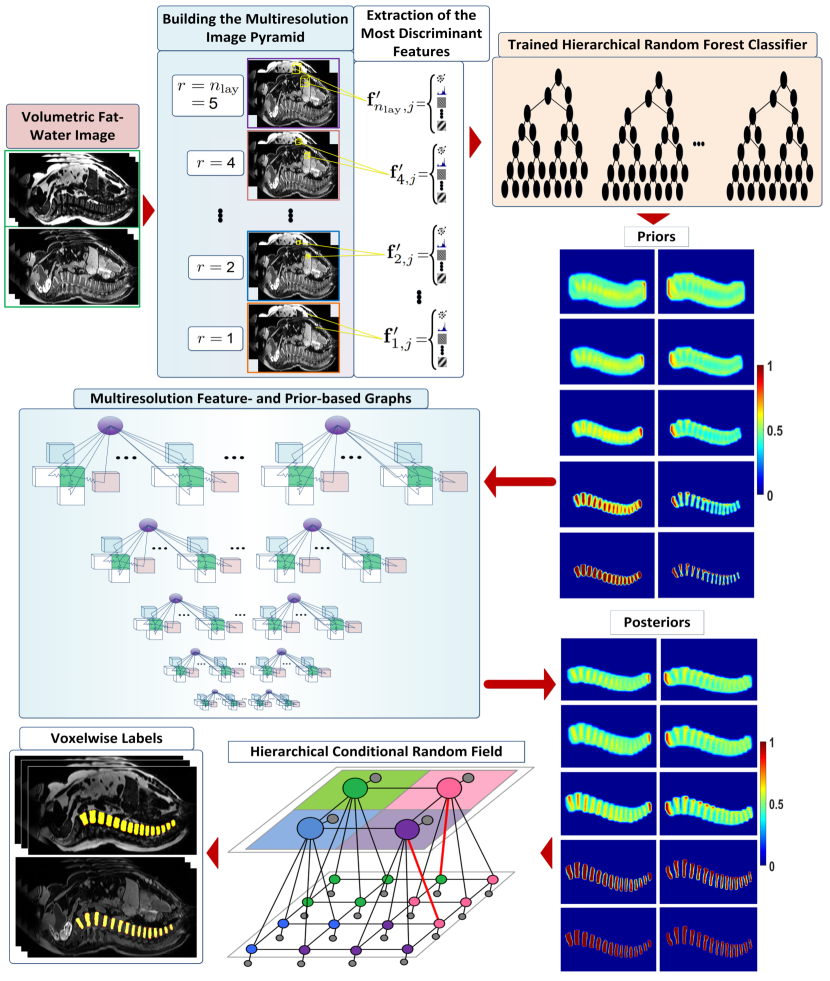

More specifically, the multiresolution neighborhood graphs estimated the classification posteriors of the multiresolution samples by using the aforementioned information except for (5), (7), and (8). The hierarchical graph fused these multiresolution posteriors into the hierarchically consistent labels by using the information indicated by (5), (7), and (8). This way, the proposed graphs could improve the classifications of the hierarchical quadratic random forest classifier proposed in [Fallah 2018a, Fallah 2018b, Fallah 2019b, Fallah 2019a]. This resulted in a classification pipeline depicted in Figure 4. At the end of this pipeline, the hierarchically consistent labels got evaluated against their corresponding reference labels . If , then these evaluations were with regard to the selected hyperparameter values for the graphs. If , then these evaluations revealed the overall classification performance of the proposed pipeline after optimizing all the parameters.